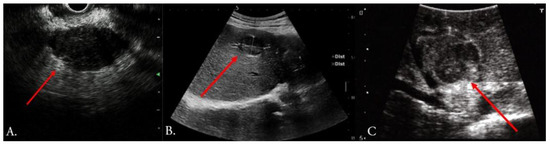

3.1. Ultrasound

- Bartos, A.; Iancu, I.; Ciobanu, L.; Badea, R.; Sparchez, Z.; Bartos, D.M. Intraoperative ultrasound in liver and pancreatic surgery. Med. Ultrason. 2021, 23, 319–328. [Google Scholar] [CrossRef] [PubMed]

- Torzilli, G.; Leoni, P.; Gendarini, A.; Calliada, F.; Olivari, N.; Makuuchi, M. Ultrasound-guided liver resections for hepatocellular carcinoma. Hepatogastroenterology 2002, 49, 21–27. [Google Scholar] [PubMed]

- Sietses, C.; Meijerink, M.R.; Meijer, S.; van den Tol, M.P. The impact of intraoperative ultrasonography on the surgical treatment of patients with colorectal liver metastases. Surg. Endosc. 2010, 24, 1917–1922. [Google Scholar] [CrossRef]

- Hoch, G.; Croise-Laurent, V.; Germain, A.; Brunaud, L.; Bresler, L.; Ayav, A. Is intraoperative ultrasound still useful for the detection of colorectal cancer liver metastases? HPB 2015, 17, 514–519. [Google Scholar] [CrossRef] [PubMed]

- Torzilli, G.; Montorsi, M.; Donadon, M.; Palmisano, A.; Del Fabbro, D.; Gambetti, A.; Olivari, N.; Makuuchi, M. “Radical but conservative” is the main goal for ultrasonography-guided liver resection: Prospective validation of this approach. J. Am. Coll. Surg. 2005, 201, 517–528. [Google Scholar] [CrossRef]

- Sahani, D.V.; Kalva, S.P.; Tanabe, K.K.; Hayat, S.M.; O’Neill, M.J.; Halpern, E.F.; Saini, S.; Mueller, P.R. Intraoperative US in patients undergoing surgery for liver neoplasms: Comparison with MR imaging. Radiology 2004, 232, 810–814. [Google Scholar] [CrossRef]